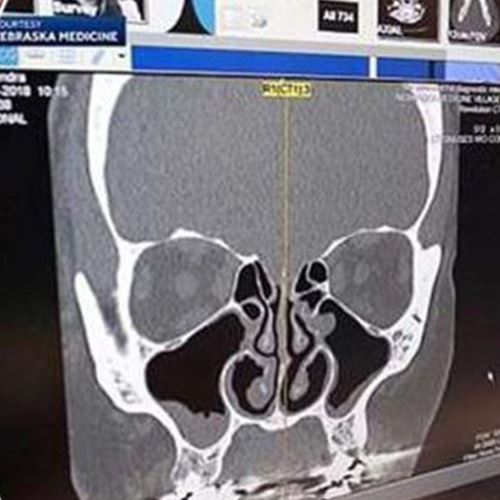

Itu yang dialami Kendra Jackson apabila cecair yang disangkanya hingus rupa-rupanya cecair cerebrospinal (CSF) yang datang daripada otaknya.

Menurut laporan Klinik Cleveland, kebocoran CSF terjadi apabila cecair di kawasan otak mengalir melalui satu lubang pada tengkorak yang biasanya berpunca daripada kecederaan traumatik.